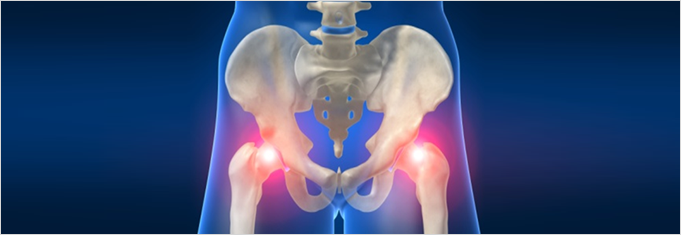

고관절 통증 증상 - 퇴행성 고관절염

퇴행성 고관절염인 경우에는 뼈사이 간격이 없어요. 연골이 마모되고 노화가 진행되면서 퇴행성 고관절염이 발생해요.

퇴행성 고관절염 초기에는 소염 진통제, 연골 보호제 등 약물 치료와 휴식, 적당한 운동을 병행하며 경과를 살피고 치료를 해야 해요. 고관절 통증 증상이 완화되지 않다면 관절 수술을 해야 해요.